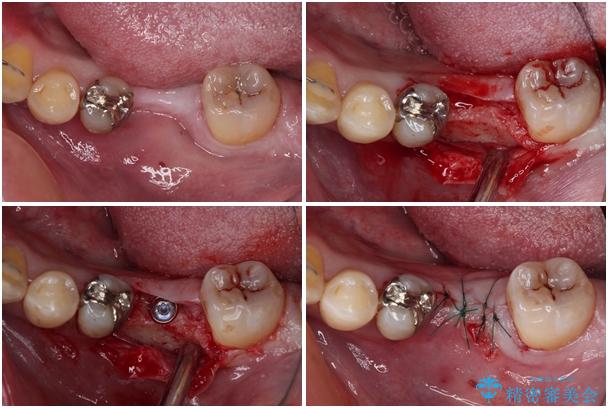

左右下顎の大臼歯は、ともに歯根が破折しており、抜歯が必要な状態でした。

放置したことで炎症による骨吸収が顕著であるため、骨造成を併用してインプラント埋入を行うこととしました。

治療途中

• 割れてしまった奥歯とデコボコの前歯 矯正治療とインプラント治療 治療途中画像